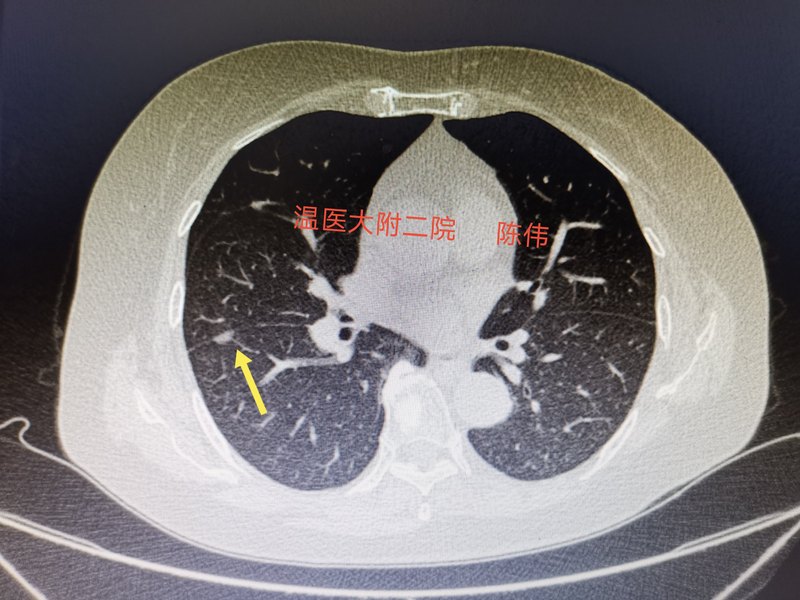

一個(gè)肺結(jié)節(jié)讓72歲的患者失眠3天下午門診來了一位老者,他丈夫和女兒陪同,見到我說我肺里面有多發(fā)結(jié)節(jié),是不是需要手術(shù),還說我不想手術(shù),打開CT一看肺內(nèi)多發(fā)結(jié)節(jié)很多都是AI找出來的結(jié)節(jié),一些是血管的斷面,還有幾個(gè)是鈣化和胸膜的皺壁,最后剩下兩個(gè)結(jié)節(jié),一個(gè)位于胸膜下,基本可以判斷是肉芽腫,最后還剩一個(gè)結(jié)節(jié),就是下圖中黃色箭頭所指 老人家說就這個(gè)結(jié)節(jié)最大,是不是要手術(shù)?因?yàn)樗€有一個(gè)化驗(yàn)結(jié)果(細(xì)胞角蛋白)高,我看了下就0.45,正常臨界值是0.33,在旁邊的女兒也說這個(gè)也高,在其它醫(yī)院也看了,都不確定,她母親又特別擔(dān)心,怕做手術(shù)。 仔細(xì)分析這個(gè)結(jié)節(jié),位于胸膜下呈磨玻璃樣改變,似乎有血管穿行,從理論上看,再加上細(xì)胞角蛋白升高,最大長徑也快1cm,一不小心就會(huì)建議她做手術(shù)。 和患者強(qiáng)調(diào)她肺內(nèi)這個(gè)最擔(dān)心的結(jié)節(jié)已經(jīng)被她監(jiān)視了,其它都不是結(jié)節(jié),讓她半年后再做一次肺部HRCT檢查復(fù)查,就算那時(shí)增大了也有時(shí)間處理。她反復(fù)問我這個(gè)不會(huì)到時(shí)增大到來不及處理吧,對(duì)于肺結(jié)節(jié)的認(rèn)知,很多人最怕的就是肺癌,更怕發(fā)現(xiàn)了以后來不及手術(shù),反復(fù)和她強(qiáng)調(diào)沒有關(guān)系,來的及,她才放下心來,他丈夫也說今晚可以睡個(gè)安穩(wěn)覺了。